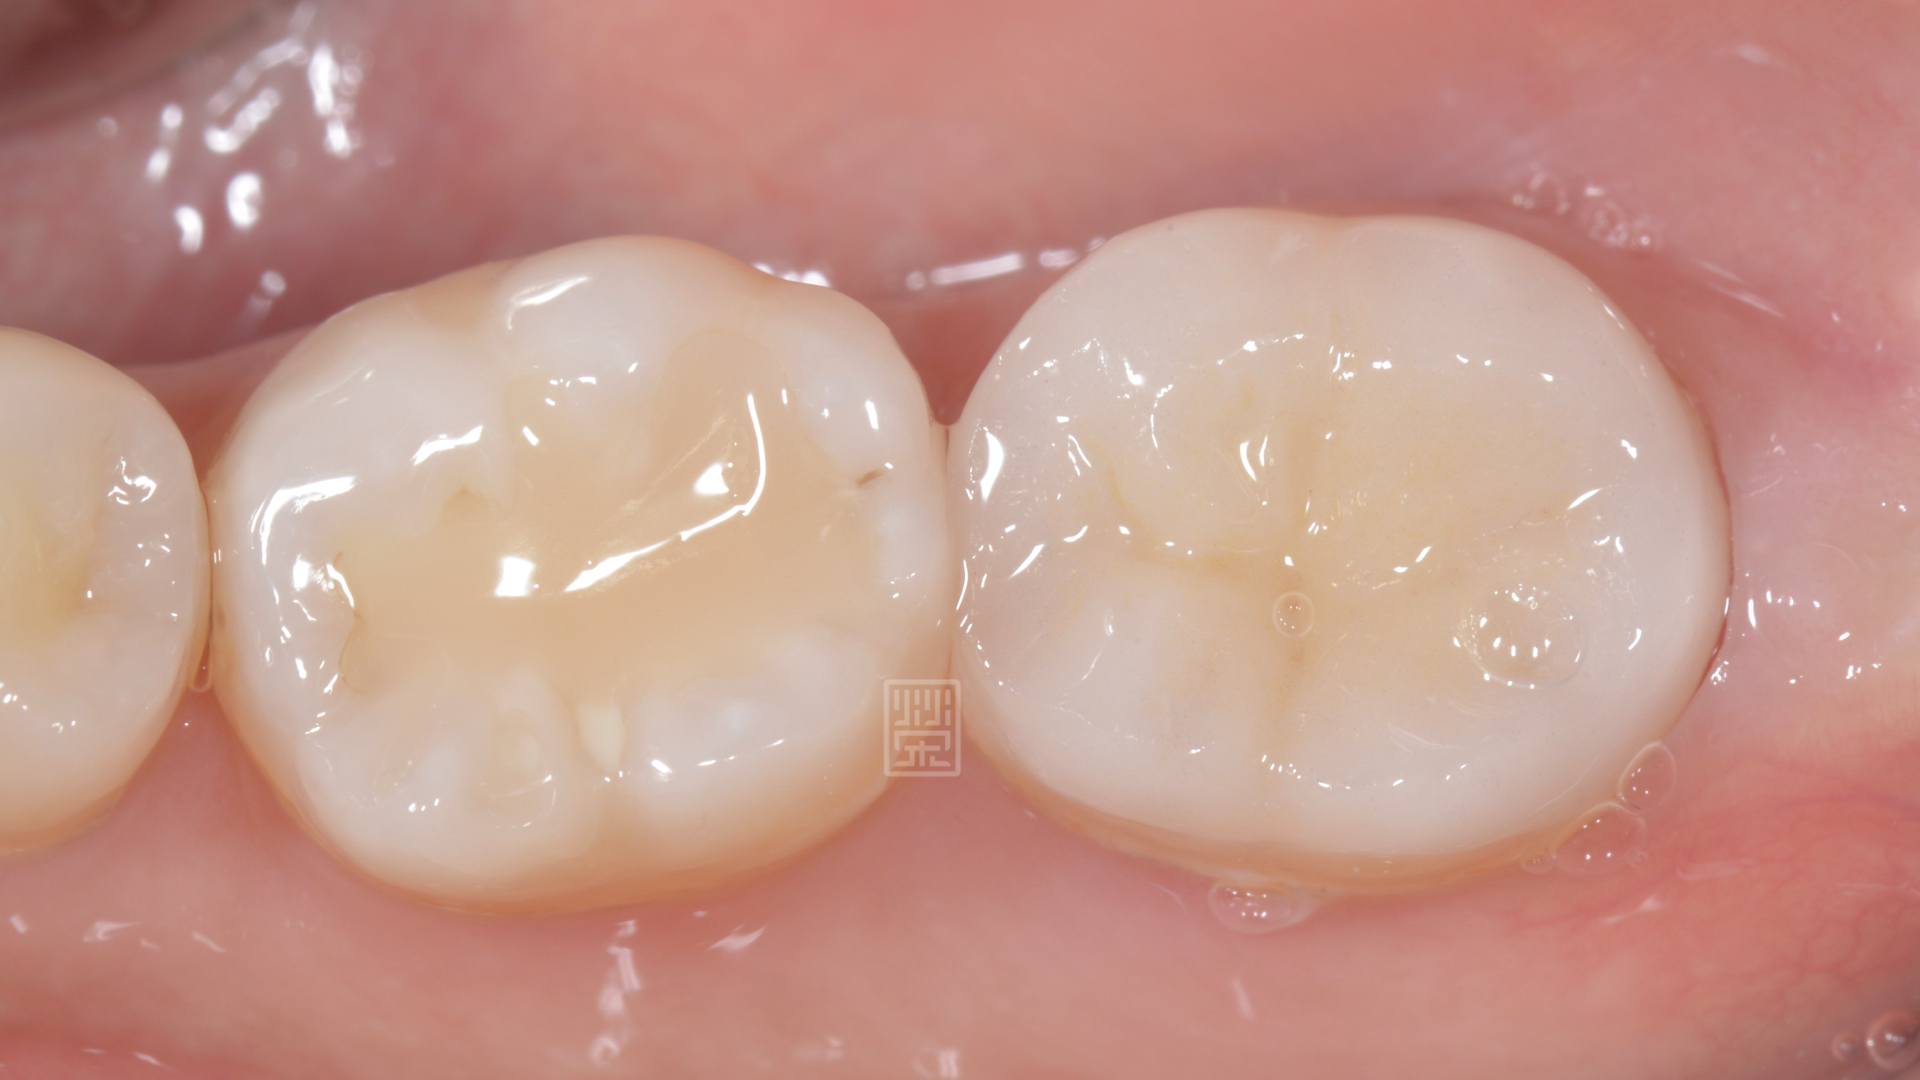

牙齒最後有填補